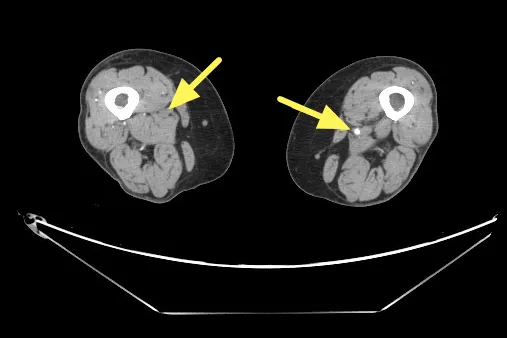

电脑断层血管摄影显示右股动脉脉阻塞。联新医院提供

杨凯迪指出,近期诊治一位64岁长期洗肾的女性患者,数月来反复出现下肢刺痛,夜深与洗肾后特别明显,同时右小腿与脚踝各有一处约3x5公分久未愈合的慢性伤口。整形外科医师清创时发现伤口几乎没有出血,转介心脏血管外科,经「踝臂血压指数(ABI)检查」左右脚分别为仅约0.67及0.64,代表下肢血流循环不良。电脑断层血管摄影更显示双侧股动脉及腘动脉严重狭窄。